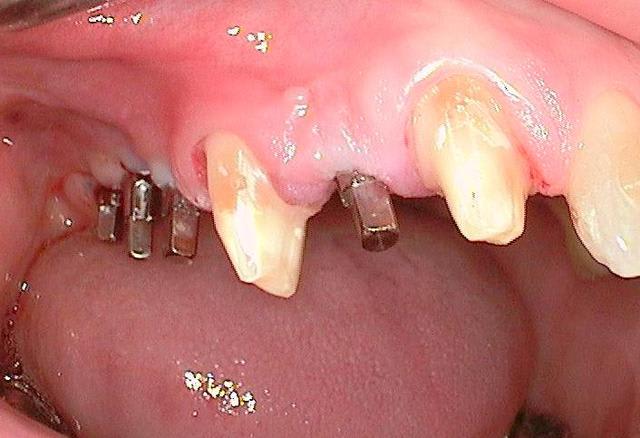

je voulais parler de ce fact pour les implants courts:minimum 4mm os vertical peut suffire (pour eviter un sinus lift externe de tatum) . dans ma pratique depuis quelques années je vois que ca marche , quelques cas cliniques des années passées.

j´ai oublié : 4mm plus 2mm( gagnés par un sinus lift interne)

oui effectivement c est preferable des implants pas agressifs, sur la photo 7 on se rends plus compte que la pointe est plate...